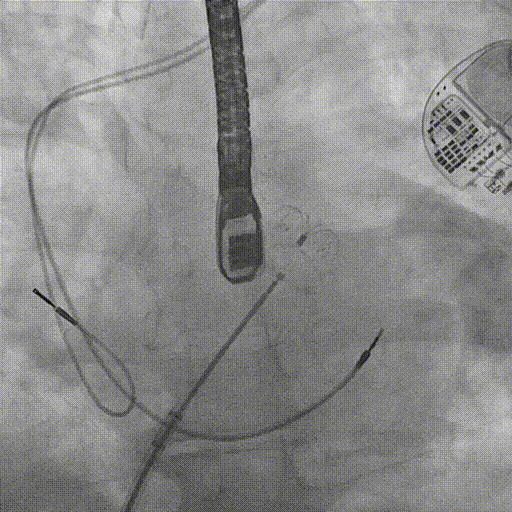

Και στο ηλεκτροφυσιολογικό εργαστήριο: